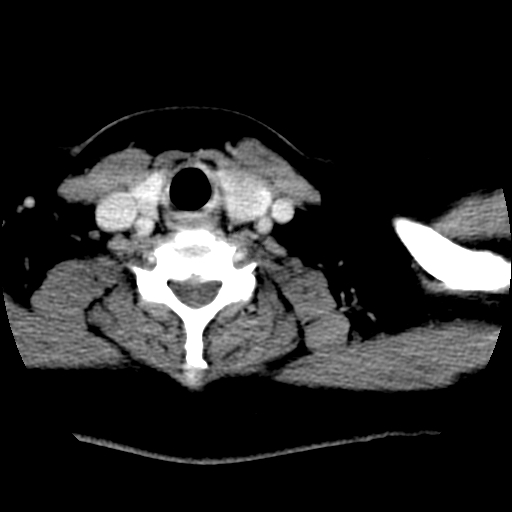

考虑左侧甲状腺结节性甲状腺肿,不排除甲状腺腺瘤。

考虑左侧甲状腺腺瘤囊变。